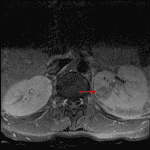

- T2/STIR signal hyperintensity and enhancement in the left L5-S1 facet joint, in the adjacent left S1 superior articular processs, L5 inferior articular process, and left L5 pedicle, and in the surrounding soft tissues without discrete peripherally-enhancing collection

Edema and enhancement in and surrounding the left L5-S1 facet joint, concerning for septic facet arthritis. Enhancement in the surrounding soft tissues without discrete peripherally-enhancing collection.